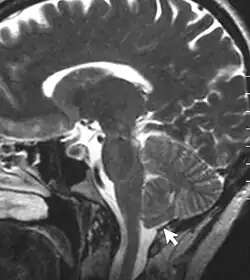

An MRI image of Chiari malformation

A T2-weighted sagittal MRI scan, from a patient with Chiari-like symptomatology, demonstrating tonsillar herniation less than 3 mm

Chronic secondary headache or orofacial pain is a result of an underlying disorder.[24] Chronic secondary headache or orofacial pain can be caused by ischemic stroke, nontraumatic intracranial hemorrhage, arteritis, unruptured vascular malformation, pituitary apoplexy, genetic vasculopathy, increased cerebrospinal fluid pressure, Chiari malformation type I, intracranial neoplasms, epileptic seizure, substance withdrawal,[24] bacterial meningitis, meningoencephalitis, viral meningitis or encephalitis, brain abscess, intracranial fungal or other parasitic infections, hypoxia, hypercapnia, dialysis, arterial hypertension, and hypothyroidism.[25]